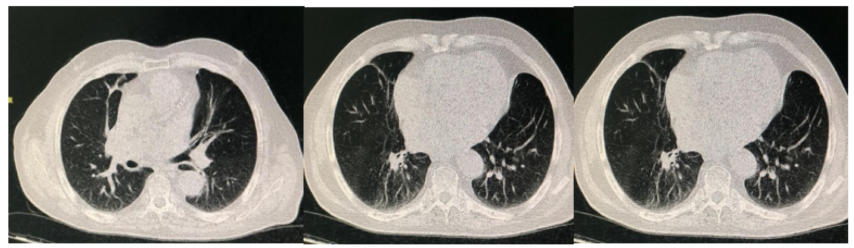

A 59-year-old female was referred to emergency department of Imam Reza hospital, Mashhad, Iran due to slowly progressive lower legs erythema and edema, as well as nausea, vomiting, stomach ache, constipation, malaise and myalgia within two previous weeks. Her medical history was notable for a completely treated pulmonary tuberculosis 8 years ago. Due to deterioration of general condition and progressive dyspnea, she was admitted in COVID-19 zone of the hospital suspicious to atypical presentation of COVID -19. During the hospitalization, blood oxygen saturation level was decreased to 70% and thus, she was admitted to intensive care unit (ICU). Lung High-Resolution computed tomography (HRCT) and chest x-ray revealed bilateral lung involvement which was more severe at the right side (fig1 and 2). Laboratory data are summarized in table 1.

Figure 2: Lung High-resolution computed tomography (HRCT) in a COVID-19 patient and pseudocellulitis lesions in legs. Fibrotic lesions and cavitation in right lung are due to old tuberculosis.